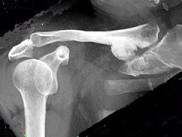

- 单项选择题如图所示,可能性最小的诊断是 ( )

A、骨瘤

B、骨肉瘤

C、陈旧性外伤

D、外生骨疣

E、以上都不是